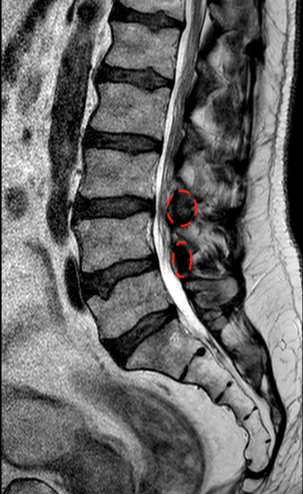

Se han marcado los ligamentos interlaminares

El paciente está asintomático en decúbito y la RM se obtiene en decúbito. La fisiopatología de la claudicación neurógena de la marcha es mecánica: de pie o andando la carga de los discos se incrementa, además, la posición erguida provoca frecuentemente que se incremente la lordosis respecto al decúbito por lo que los ligamentos («amarillos» o interlaminares e interespinosos) protruyen en el canal. La descompresión interlaminar no modifica la distribución de cargas, pero al eliminar las partes blandas que protruyen se mejora la compresión y la claudicación neurógena de la marcha.